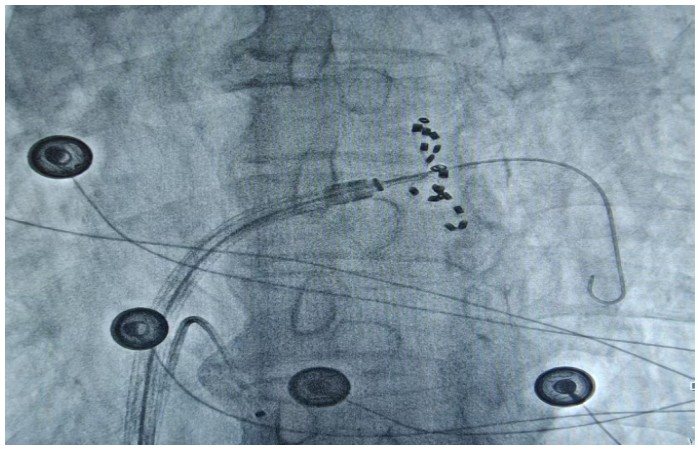

通訊員何紅丹報道:2025年1月17日,衡陽市中心醫(yī)院心血管內(nèi)科趙慶禧主任醫(yī)師團隊與心血管內(nèi)科電生理團隊協(xié)作,在全麻下成功為一名72歲的男性患者實施了陣發(fā)性房顫FARAPULSE脈沖電場消融手術(shù)。此次手術(shù)為目前全球最先進(jìn)的PFA消融導(dǎo)管上市后全國首批臨床應(yīng)用,在湘南地區(qū)首次開展,能更精準(zhǔn)地作用于目標(biāo)區(qū)域,減少對周圍組織的損傷,極大程度降低并發(fā)癥的發(fā)生,具有更高的安全性。

趙慶禧介紹,房顫是常見于老年人的心臟問題,通俗的講就是心臟“亂跳”。發(fā)生房顫時患者心慌心悸難忍,極易誘發(fā)腦卒中等惡性后果,嚴(yán)重危害生命健康。目前,房顫的治療方法包括藥物治療和傳統(tǒng)導(dǎo)管消融。相較于藥物治療和傳統(tǒng)導(dǎo)管消融,脈沖電場消融可選擇性的損傷心肌,而保留血管、神經(jīng)及心臟周圍組織。更快的消融脈沖電場消融(PFA)技術(shù)是最新的消融技術(shù),它能通過高壓電脈沖,實現(xiàn)消融點細(xì)胞凋亡的目的,達(dá)到抑制紊亂心律發(fā)生的作用。與傳統(tǒng)消融技術(shù)相比,脈沖電場消融具有更高的組織選擇性、更快的消融速度以及更低的貼靠要求,成為臨床迫切需要的突破性創(chuàng)新治療方法,為患者帶來了新的選擇和新的希望。